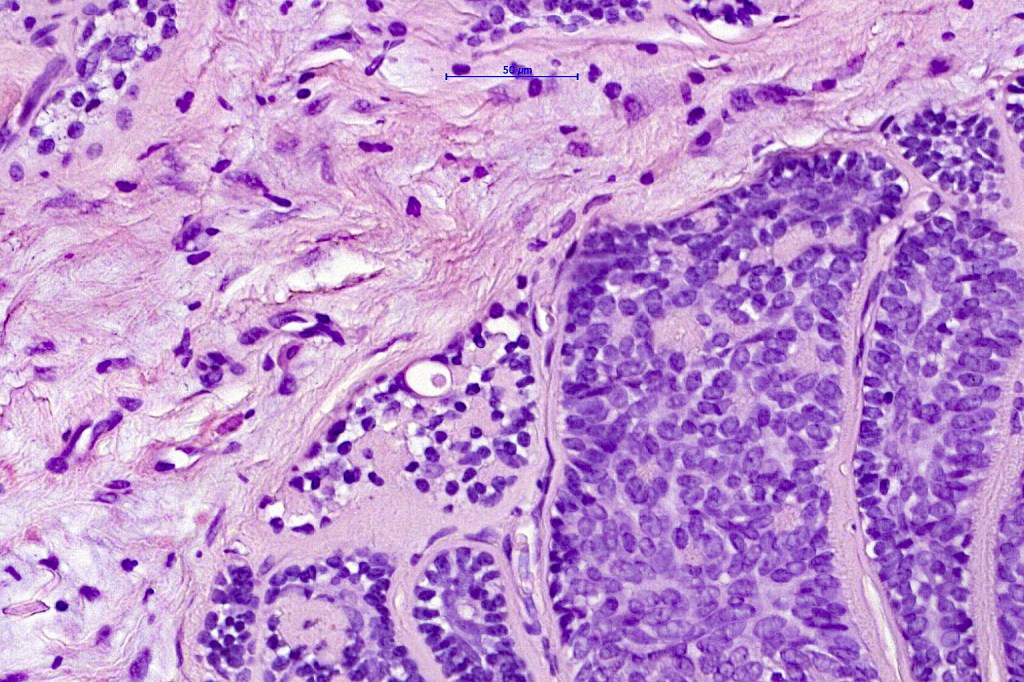

Histological features

•Dermal based

•Jigsaw/mosaic pattern arrangement of variably sized lobules of tumor cells with surrounding think, eosinophilic hyaline basement membrane

•Intralobular hyaline basement membrane material droplets

•Outer layer of intensely basophilic small cells surrounding larger central cells with pale staining or eosinophilic cytoplasm & vesicular nuclei

•Ductal differentiation